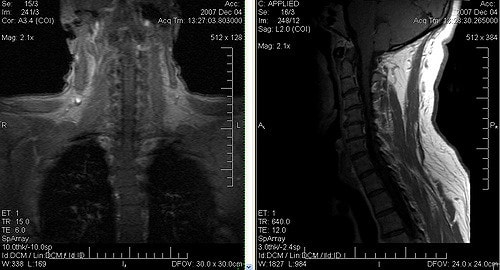

- МРТ шеи и головы.

Иногда болит шея и затылок, и причина остается неясной. В таких случаях комплексное исследование сосудов и магнитно-резонансная томография помогут установить диагноз, подтверждающий мигрень. Это заболевание может затрагивать не только голову, но и шею.